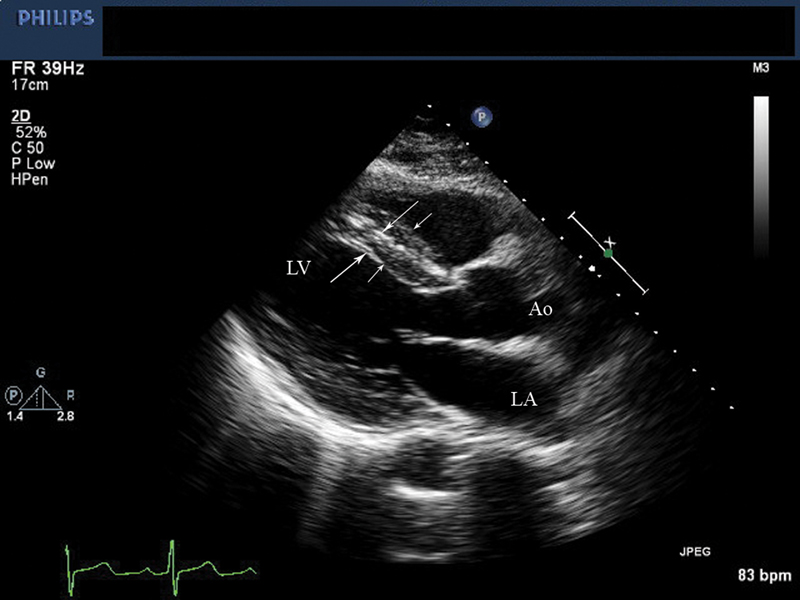

فحوصات تشخيصية لبعض امراض القلب والشرايين التاجية